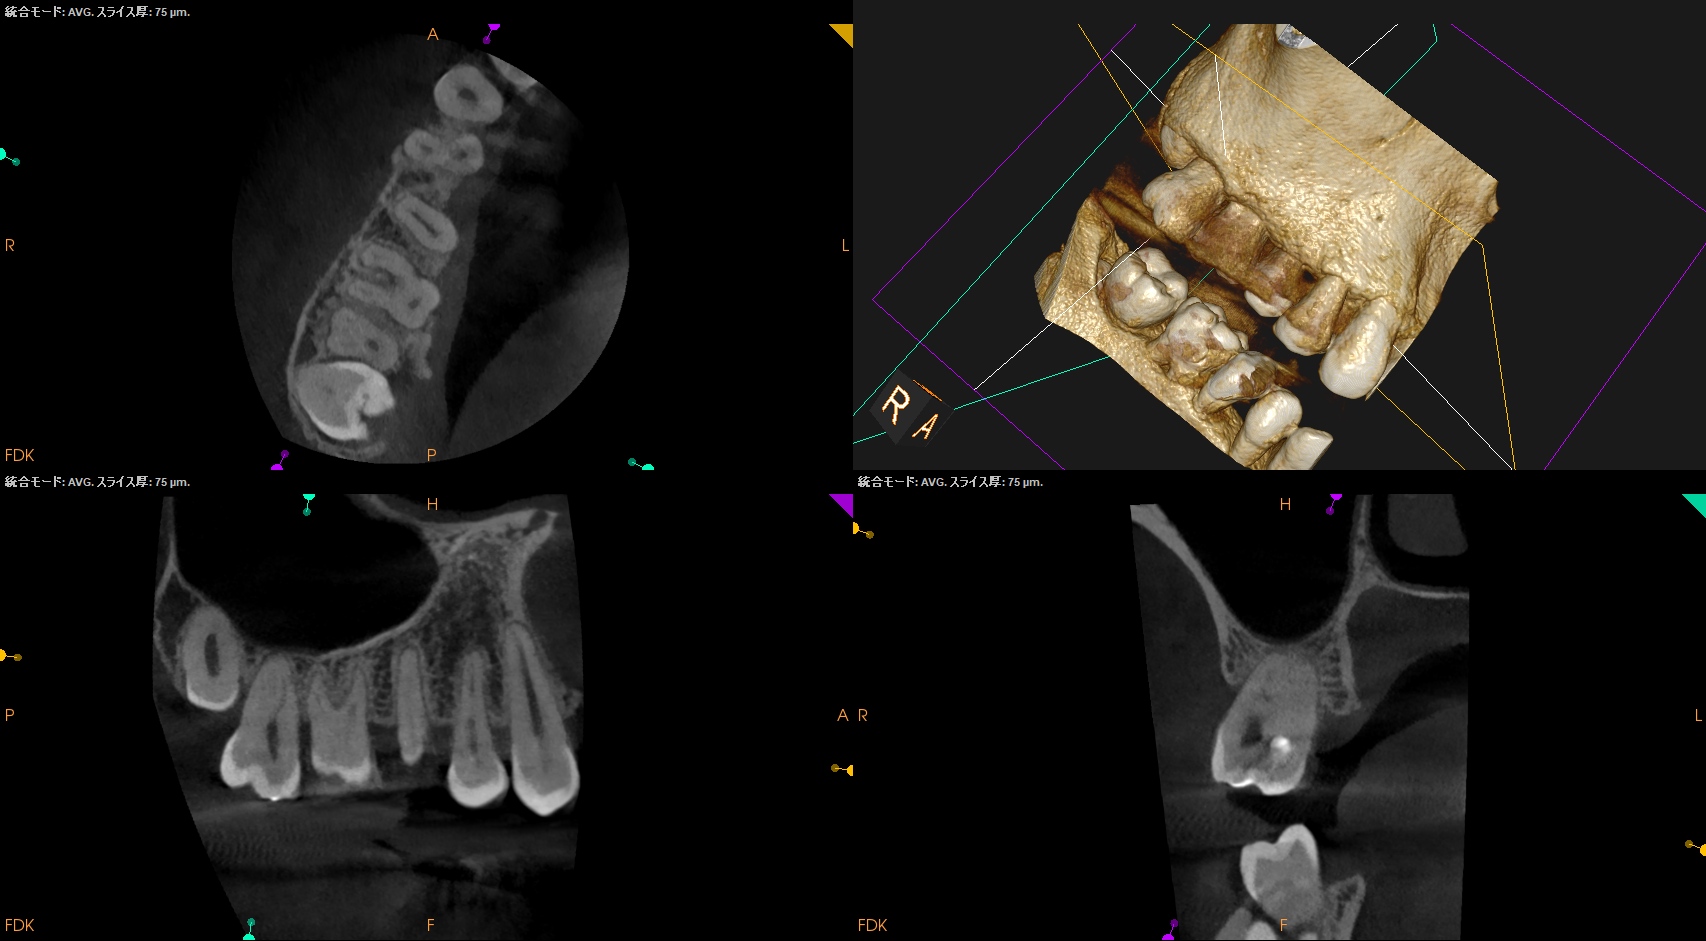

PA, CBCTも撮影した。

#14と同じような症状がある#2,5であるが、

#2

MB

DB

P

#5

B

無傷の#5にも同じような症状がある。

ということは…

#14の咬合痛?のようなものは病気でなく、そう感じるという臨床的状態で, それだからといって治療を要するものではないだろう

ということがわかる。